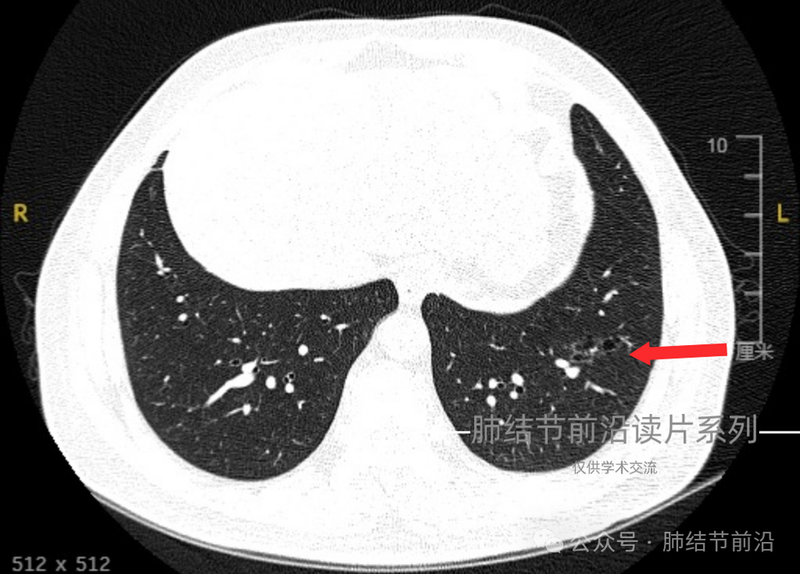

47岁中年男性,不吸烟。一个月前体检发现左下肺阴影。形态为不规则磨玻璃影,伴有空泡。

2024年9月,至门诊复查,阴影未吸收。CT见左下肺磨玻璃影,不规则。此种很容易误判为炎症。但更重要的是,磨玻璃中央有空泡。而且空泡连续成串。并1个月随访没有变化,那么此种就为典型的肺腺癌表现。